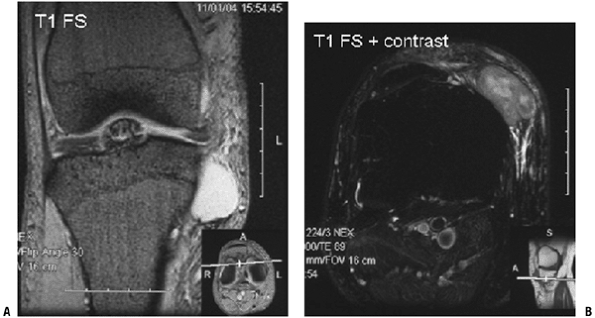

MRI alone cannot differentiate benign tumors from malignant ones. Lipomas and synovial cysts/ganglions are exceptions.

-

Lipomas have a characteristic appearance

on MRI, with uniform homogenous fatty signal on all sequences and loss

of signal on the fat-suppression sequences (Fig. 2-6). -

Cysts do not demonstrate central enhancement with gadolinium (Fig. 2-7).

Not all small masses near a joint

(especially the knee and wrist) are ganglions. Unfortunately, small

soft tissue sarcomas can occur in and around joints. When in doubt,

obtain an MRI with contrast to differentiate cystic masses from solid

masses (Fig. 2-8). -

Figure 2-6 Intramuscular lipoma. (A) On the T1-weighted image, the intramuscular mass is the same signal as the subcutaneous fat. (B)

On the fat-suppression T2 image, the mass remains homogenous with a

uniform loss of signal. Post-contrast enhanced images would not show

any enhancement.-

Figure 2-7 This parameniscal cyst demonstrates homogenous dark signal and bright signal on the T1-weighted (A) and T2-weighted (B and C) images, respectively. (C)

With the administration of gadolinium contrast, note the lack of

central enhancement, with enhancement peripherally only. The

enhancement pattern is characteristic for cystic structures.-

Figure 2-8 (A)

This small, well-encapsulated mass near the knee joint demonstrating

homogenous high signal on the T1-weight fat-suppressed image could

easily be mistaken for a cyst. (B)

Contrast administration reveals heterogeneous, central enhancement,

proving this is a solid mass. Biopsy revealed an extraskeletal myxoid

chondrosarcoma.